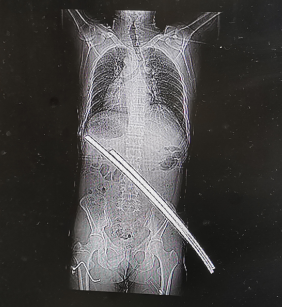

8月1日,正在17楼高空作业的张师傅踩在一块悬空搭建的木板上,不料木板突然之间断裂,张师傅开始往下掉,掉至15楼时,两根钢筋接住了他,并从其臀部向腰部斜行刺穿。顿时,张师傅感觉到疼痛,身体动不了了。他赶紧掏出口袋里的手机,打给工友:“老李,快喊几个人来救我,我从17楼掉到了15楼,被两根钢筋挂住了。”工友赶来,立刻拨打了120电话,并将钢筋截断救下张师傅。

当天,普外科高庆安医生接到急诊通知后,立刻为张师傅完善各项术前检查。通过CT检查,诊断钢筋只是刺穿张师傅的肌肉,万幸的是并未累及重要脏器和血管,肋骨骨折、左肘部皮肤擦伤,张师傅暂无生命危险。高医生手术团队为张师傅进行了“腰背部清创+异物取出术”,术中从右臀部拔除钢筋,切开皮肤及皮下组织进行清创,探查见创面污染严重,混有砂砾、油灰等。手术共进行了两个小时,比较顺利。术后张师傅情况稳定。

高医生介绍,张师傅比较幸运,虽然是贯穿伤,但不是太严重。手术切口约有半米长,术后在护理上需要特别注意防止伤口感染。